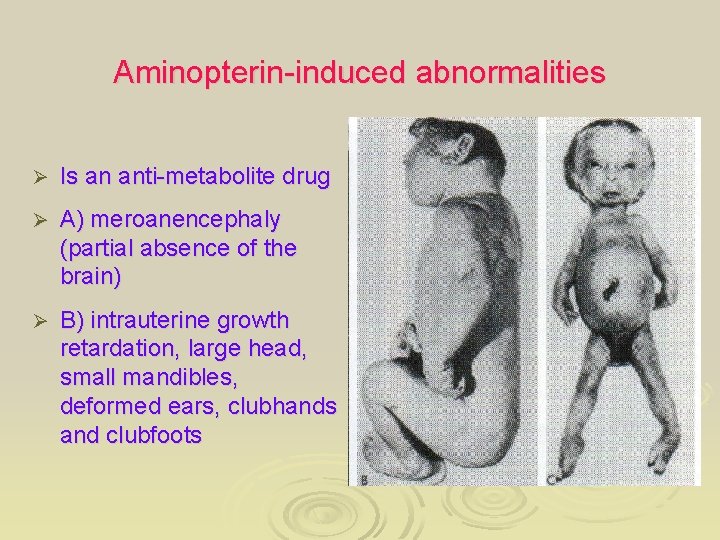

Aminopterin-induced abnormalities Ø Is an anti-metabolite drug Ø A) meroanencephaly (partial absence of the brain) Ø B) intrauterine growth retardation, large head, small mandibles, deformed ears, clubhands and clubfoots